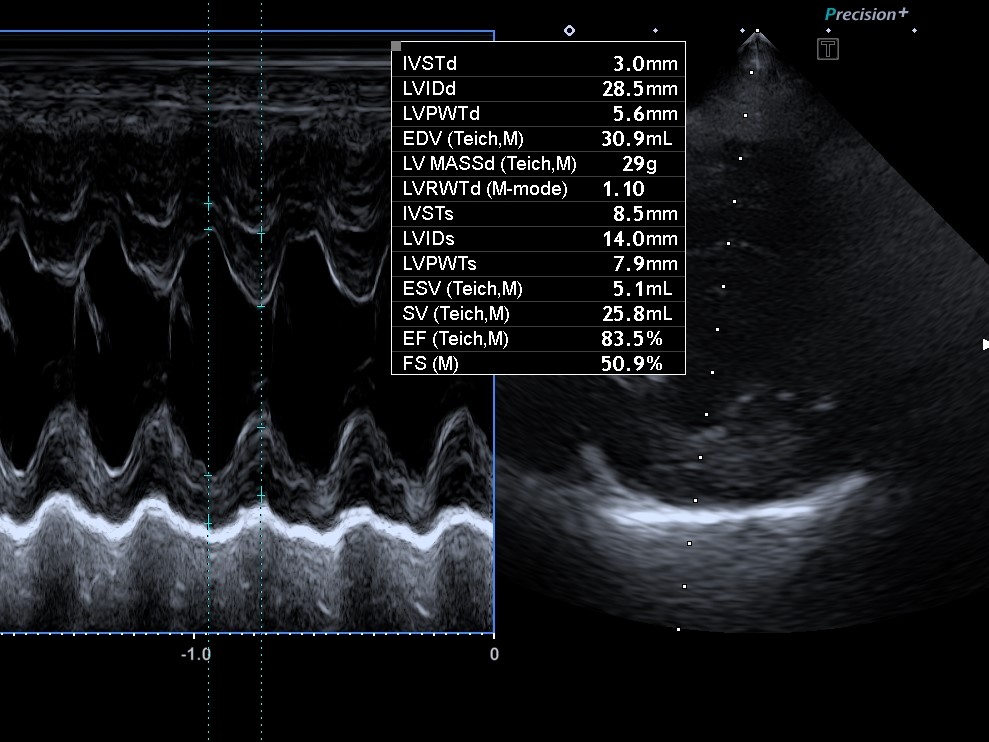

강아지 심장병 2단계란?강아지가 평소보다 쉽게 숨을 헐떡이고, 산책 후 유난히 피곤해한다면 단순한 노화의 징조로 넘기기 어려울 수 있다.특히 심장병 2단계는 보호자가 보기에 뚜렷한 증상이 나타나기 시작하면서도,조기 진단과 일상 관리만 잘해도 진행을 늦출 수 있는 시기이기 때문에 매우 중요하다.이 글에서는 강아지 심장병 2단계의 정의, 주요 증상, 진단 과정, 약물 치료, 식단 및 생활 관리 팁까지수의사가 아닌 보호자 입장에서 꼭 알아야 할 현실적인 조언을 중심으로 자세히 설명한다.당신의 강아지가 더 오랫동안 건강하게 숨 쉴 수 있도록, 지금 필요한 지식들을 하나씩 정리해보자. 심잡음이 청진에서 확인됨아직 증상은 거의 없음 (호흡 이상 없음)엑스레이나 심장 초음파에서 구조적 변화가 일부 보임운동 후 피로감..